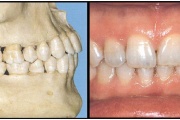

Normaalse jäävhammaskonna pilt küljelt ja eest vaadatuna.

Ülemise hambakaare kitsenemine ehk tagumiste hammaste risthambumus.